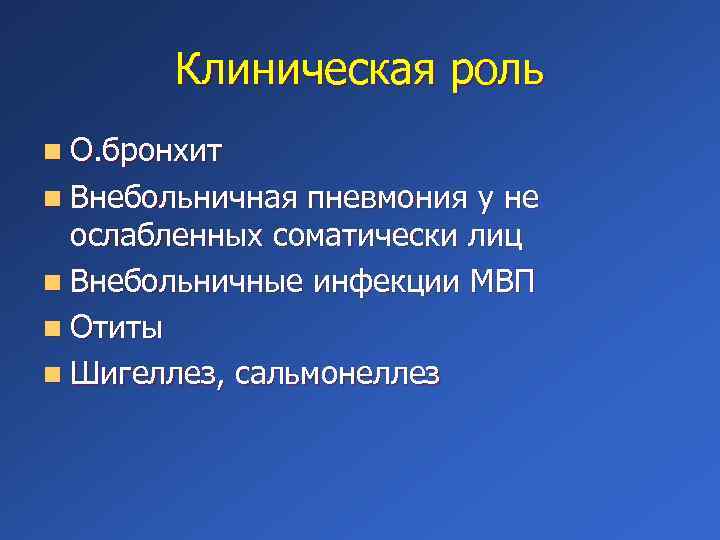

Острая внебольничная пневмония по МКБ-10: признаки и примеры